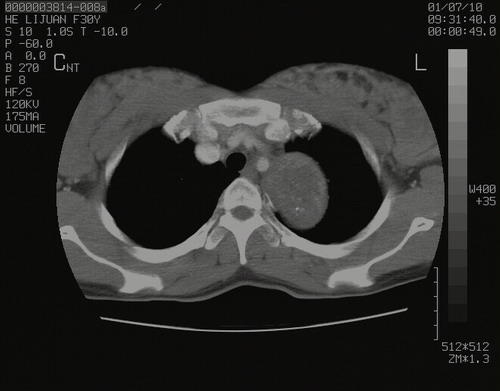

怀孕3个月时(2009-3至4月间),自述突感左侧前后胸疼痛1天,以前胸明显,随后偶感闷痛,余未见异

左肺尖脊柱旁沟肿块,境界清楚,边缘光滑,密度不均,内有多发点片状钙化,考虑良性肿瘤,骨软骨瘤或神经源性肿瘤可能,肺错构瘤不除外。

左后上纵隔见一类圆形肿块影,外侧边界清,密度不均匀,内可见点状钙化影,增强呈不均匀强化,考虑神经源性肿瘤可能。期待病理结果。